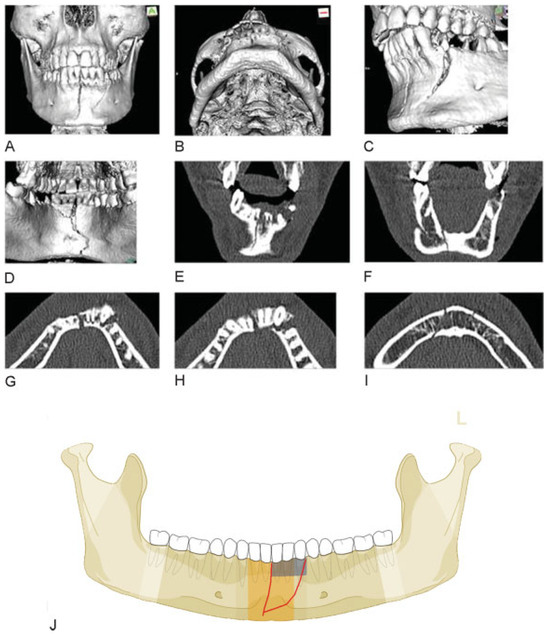

Figure 9.

Body fracture of grade 2 fragmentation extending into the symphysis. (A–D) Imaging: CT scans 3D reformatted overviews lateral, anterolateral, laterobasal, and lingual. Narrative description: A look from the outer surface shows multiple large-sized intermediate fragments confined to the mandibular body on the left in its full vertical height. The inspection of the inner aspect exhibits that the anterior tip of a large rhomboid intermediate fragment extends into the symphysis (below 32) (see shaded fragments in illustration below showing fracture pattern on lingual side, which is crucial for to code level 3). The fragmentation the body region is grade 2 and in the symphysis grade 1. (E) Code Level 3: 91 S1- B2. This case example CMTR-91-027 is made available electronically for viewing using the AOCOIAC software at www.aocmf.org/classification.